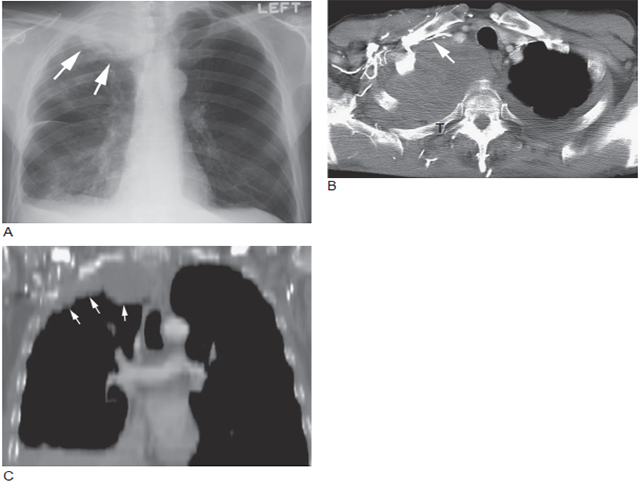

图4 肺上沟瘤

A. 胸片显示右肺尖肿块( 箭头);B. 经右肘注入对比剂行增强CT显示肿块占据肺尖部(T),右锁骨上静脉阻塞(箭头) 伴多支胸壁静脉侧支形成;C. 冠状CT 重建显示肺尖肿块( 箭头) 沿胸壁延伸